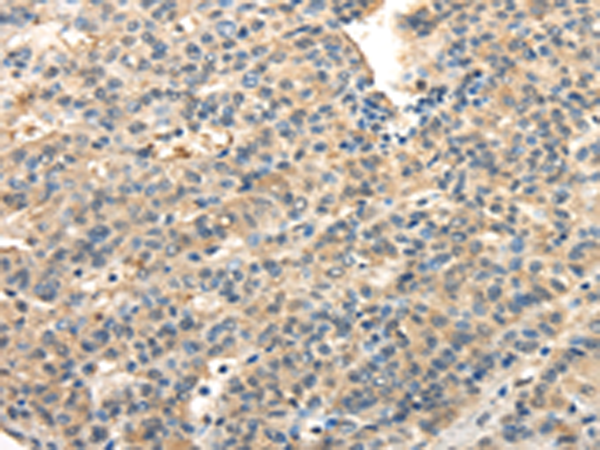

分类: 科研抗体货号: P08928别名: JTK1; IMD35应用: IHC反应种属: Human, Mouse